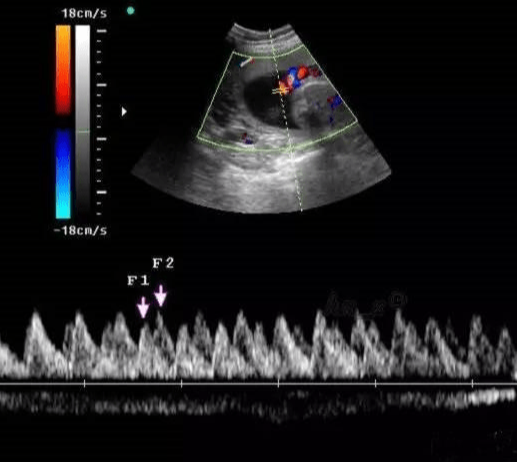

• 臍血流

臍血流

02-21

臍血流是指臍動脈收縮期最高血流速度與舒展期最低血流速度的比值、陰力指數(shù)與搏動指數(shù)等指標(biāo)來反應(yīng)血流情況。檢查臍血流是為了判斷胎兒在宮內(nèi)的發(fā)育情況。